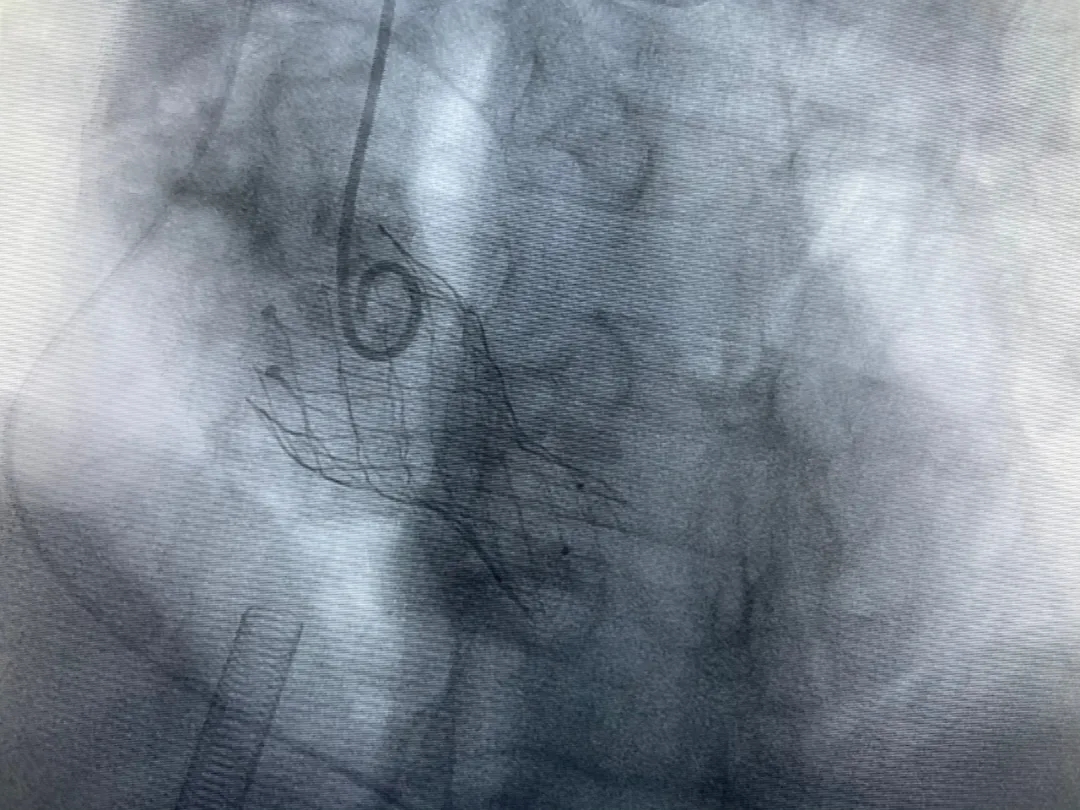

結(jié)合老人病情特點:年齡高、室壁厚、左室腔小、瓣膜鈣化嚴(yán)重,術(shù)中球囊擴(kuò)張和瓣膜釋放過程有循環(huán)崩潰可能;為降低此種風(fēng)險、最大程度提高手術(shù)成功率,張金洲副院長在術(shù)前組織了由楊金保博士帶領(lǐng)的TAVR團(tuán)隊多次反復(fù)溝通、討論,制定了各種應(yīng)急處理方案。最終經(jīng)過TAVR團(tuán)隊的默契配合,手術(shù)歷時2小時,用20#球囊預(yù)擴(kuò)張后順利植入23#主動脈瓣生物瓣膜,再次后擴(kuò)后主動脈根部造影顯示:人工主動脈瓣生物瓣位置良好,瓣葉開閉正常;冠脈顯影良好。經(jīng)食道超聲顯示:主動脈瓣葉活動度良好,主動脈跨瓣壓差約35mmHg,未見瓣周漏及明顯返流。出手術(shù)室前老人便已蘇醒,自訴憋悶癥狀完全消失。